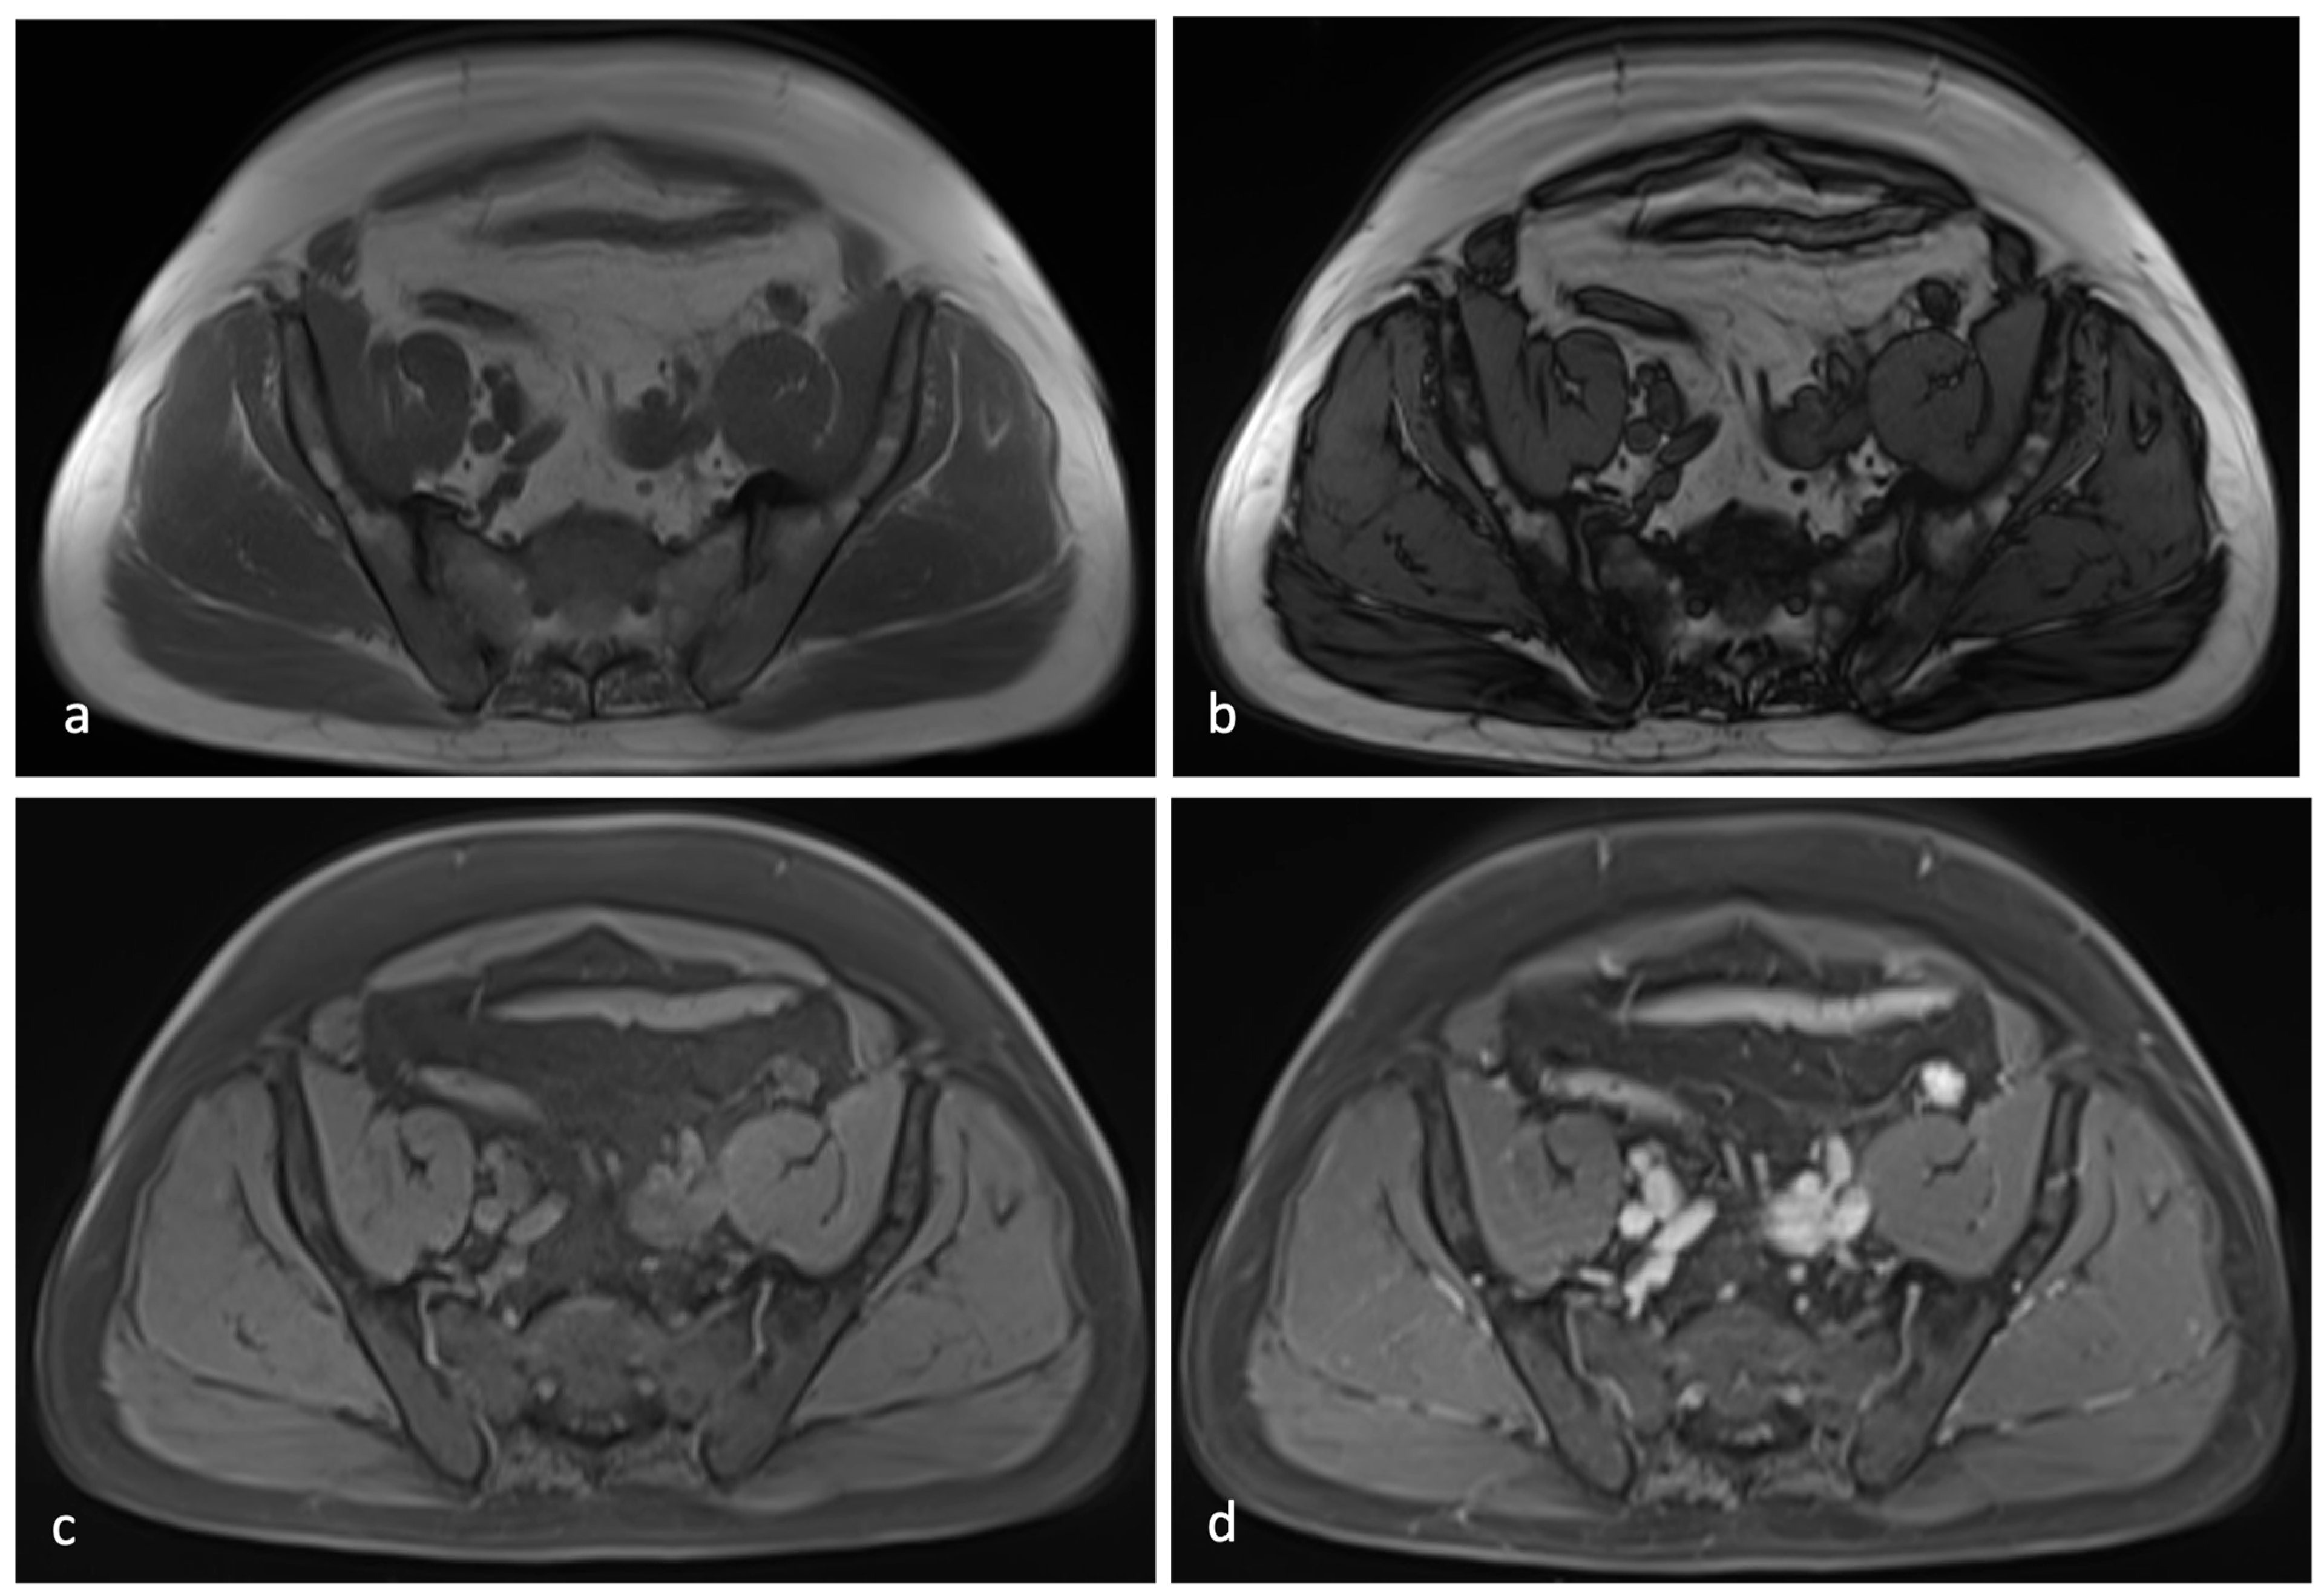

3.2. Case Presentation

4.3. Diagnostic Challenges and Imaging Limitations

- A solid homogeneous well circumscribed lesion, without calcifications, with a characteristic CT and MRI contrast enhancement, as described in many case reports in the literature;